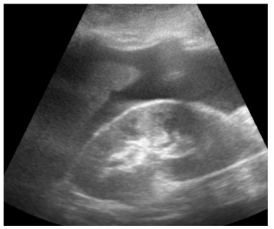

Insonação cardíaca Janela apical 5 câmaras com VTI de 9,08 cm

O nefrologista foi chamado a opinar na melhor conduta para o paciente. Para tanto, realizou uma ultrassonografia beira leito pulmonar e mensurou a velocidade integral tempo (VTI) do trato de saída do ventrículo esquerdo. Chegou, assim, à conclusão que poderia ser feita uma expansão no paciente. Com base nas imagens apresentadas, é correto afirmar que conduta recomendada pelo nefrologista está